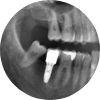

상실된 치아를 위한 선택, 임플란트

Dental Implant

영구치는 한번 빠지면 다시 나지 않습니다.

틀니와 브릿지 등 손실된 치아의 기능을 보충하는 보철물들이 있으나

많은 단점이 있어 사용에 불편합니다. 임플란트를 통해 새로운 내 치아를 탄생시켜 보세요.

유치 후에 영구치가 있다면 영구치 후에는 내 인생 세 번째 치아, 임플란트가 있습니다.